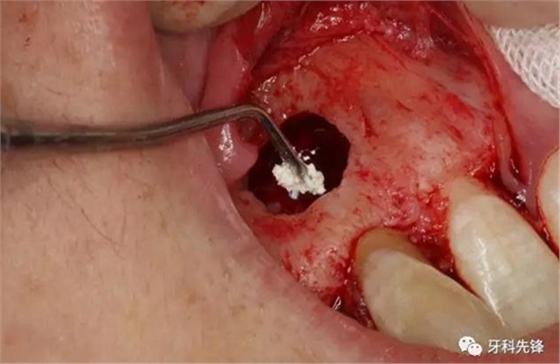

圖11.取出囊腔內(nèi)的致密團(tuán)塊。

圖12. 取出沒有完全鈣化形成的牙齒。